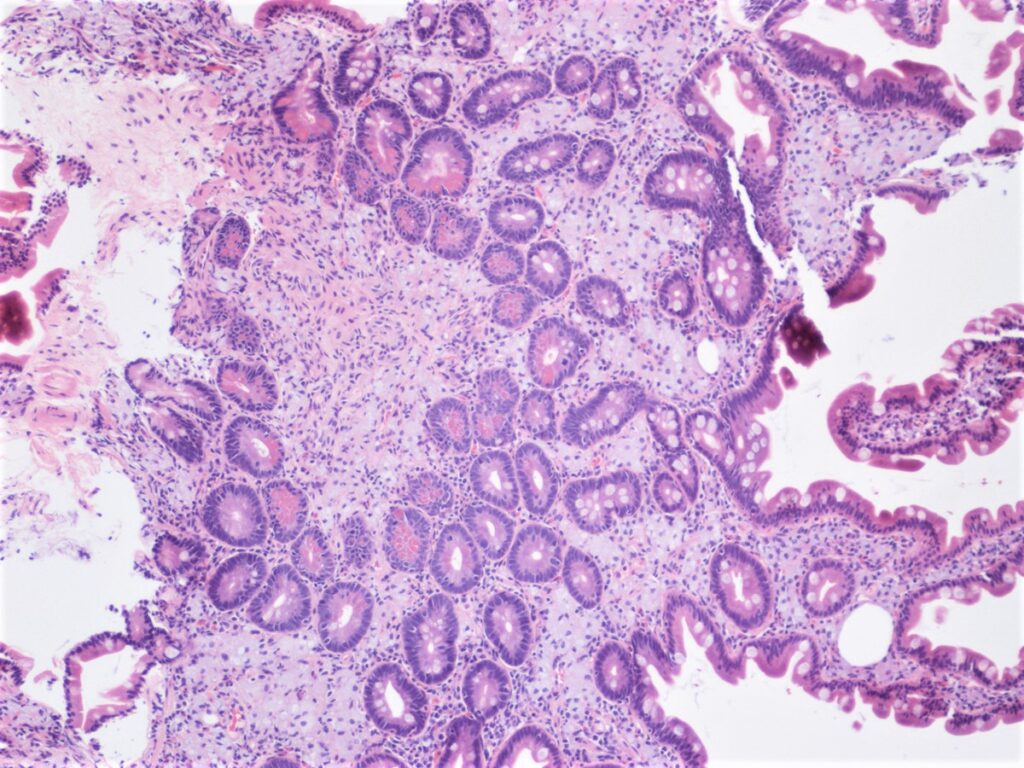

Pseudoobstrucción aguda del colon (síndrome de Ogilvie)

La dilatación masiva espontánea del ciego y del colon proximal es un fenómeno que puede presentarse en diversos contextos clínicos en pacientes hospitalizados, y es una condición que puede desencadenar…